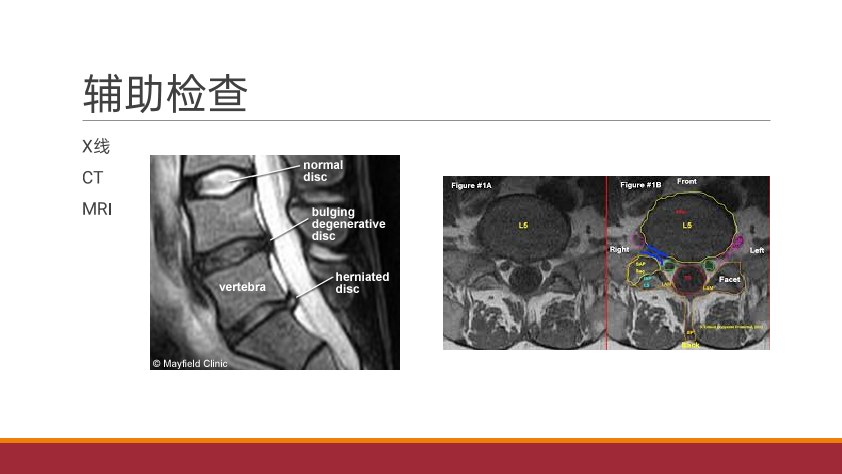

腰椎间盘突出